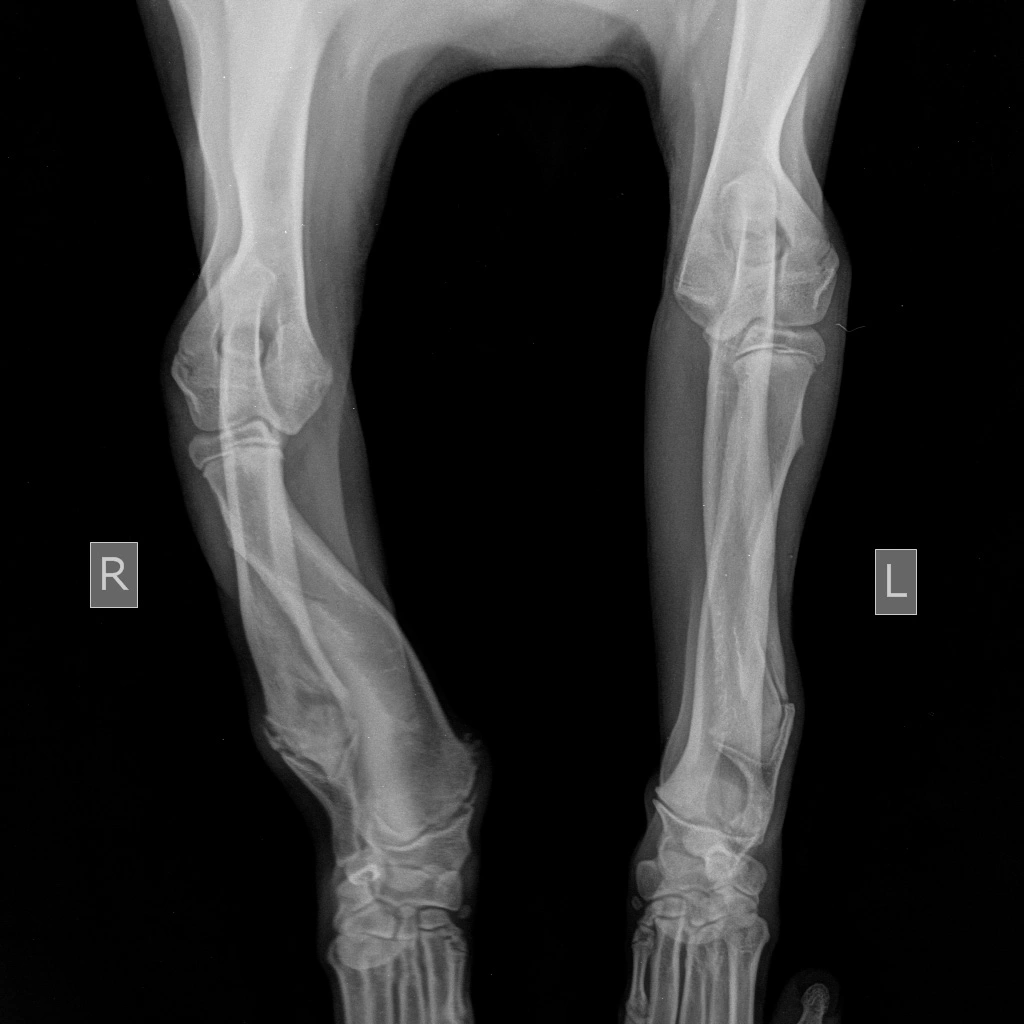

Как проводится лечение укороченной локтевой кости?

Консервативное лечение включает в себя «клеточное содержание», нормализацию кальцие-фосфорного обмена по средствам нормализации рациона и контроль боли. Однако оно редко дает хороший результат.

Хорошо зарекомендовало себя хирургическое лечение — дистальная остеотомия локтевой кости. Данная операция снимает эффект «натянутой тетивы» с локтевой кости, при этом лучевая кость продолжает расти и начинает постепенно выпрямляться за счет продолжающегося роста. Данную операцию необходимо проводить в возрасте 4-7 месяцев т.к. зона роста лучевой кости еще не закрыта.

Если в 4-5-месячном возрасте была проведена дистальная остеотомия локтевой кости и она в течение 1-1,5 месяцев не приводит к видимым улучшениям, то в кратчайшие сроки применяют методику блокировки медиального участка дистальной ростковой зоны.

У мелких и хондродистрофичных пород собак хромота развивается позднее, примерно в 6-10 месяцев и связана она в основном с подвывихом локтевого сустава. У таких пород, особенно при наличии хромоты и отсутствии видимой деформации конечности, бывает достаточно проведение только проксимальной динамической остеотомии локтевой кости, для корректировки подвывиха.

Если данные виды хирургического лечения не оказывают достаточно хорошего эффекта, т.е. у животного наблюдается хромота и присутствует визуальные различия между передними конечностями, то прибегают к такой хирургической методике как корректирующая остеотомия лучевой кости. Но данная методика может быть использована только после окончания роста костей в длину (10-12 мес.) При данной методике разрезают (метод открытого клина) либо вырезают участок лучевой кости (метод закрытого клина) и место остеотомии фиксируют накостной пластиной или внешним фиксатором. Нередко при этой операции прибегают и к артродезу запястного сустава, в случае позднего обращения владельцев животного в клинику, т.к. из-за сильного давления на запястный сустав, в нем развиваются необратимые дегенеративные изменения.